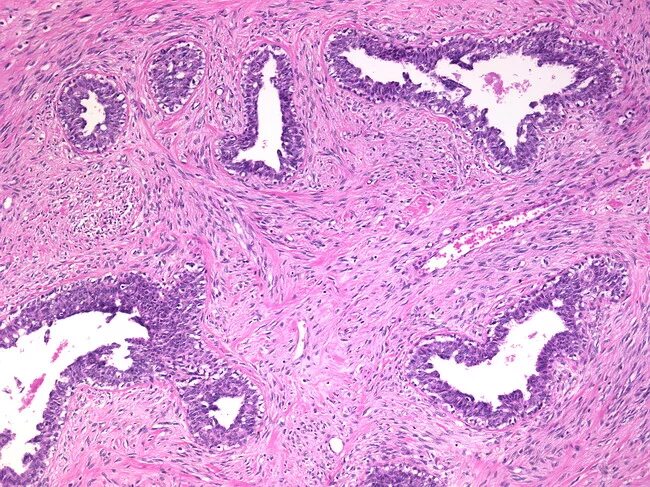

Что показала гистология замершей